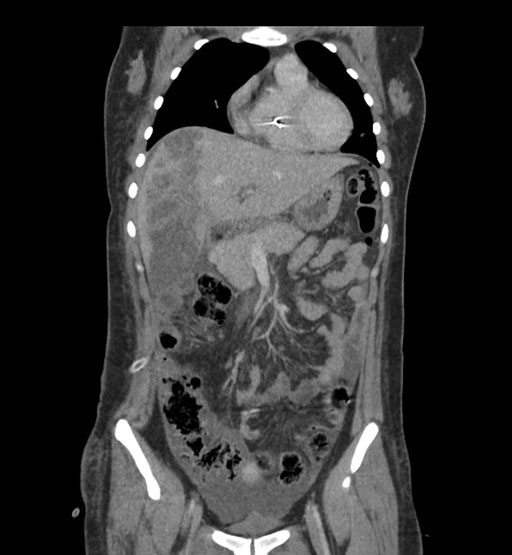

Imaging Analysis

Look through the patient's CT scan to identify any areas of concern for the necessary procedure.

Coronal Venous

Based on initial findings, which issue(s) would you be most concerned about?